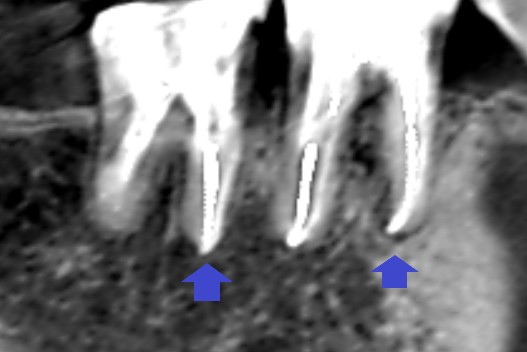

精密再根管治療6ヶ月後のCT画像です。

根の先にできていた膿の影が消失しています。